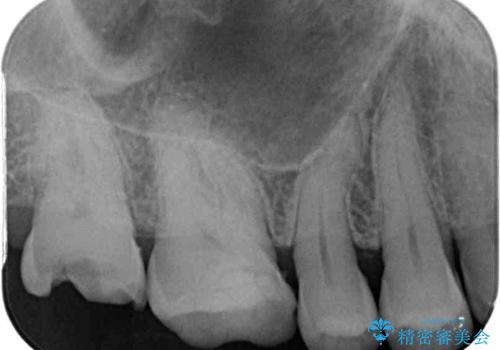

- 銀歯が外れてしまったとのことで来院された患者様です。

上顎奥の粘膜に近い部分で、外れた銀歯の下には大きく虫歯が広がっていました。

虫歯をしっかりと取り除き、ゴールドインレーにて修復することとしました。